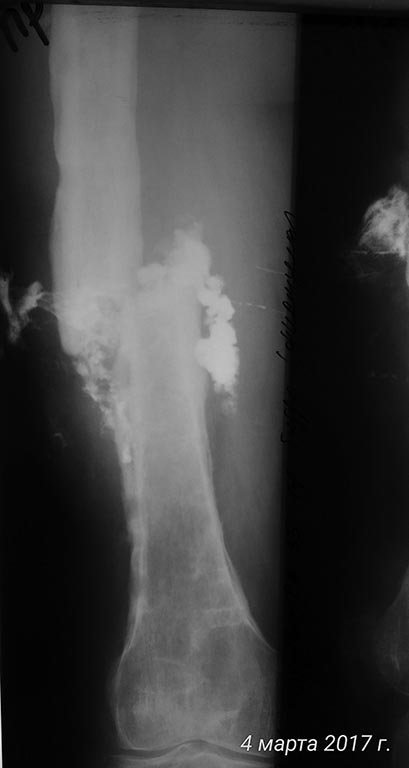

[Ortho] хронический остеомиелит с/3 бедра, свищевая форма, стадия обострения. Несросшийся перелом с/3 бедренной кости.

Вложение не в текстовом формате было извлечено…

Имя     : fistulo2.jpg

Тип     : image/jpeg

Размер  : 30228 байтов

Url     : http://weborto.net:8080/pipermail/ortho/attachments/20170305/3a1fc87a/attachment-0003.jpg